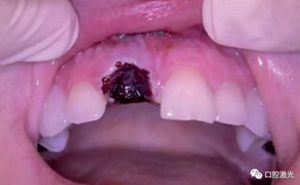

激光輔助治療術(shù)中

術(shù)后即刻,薄膜層的形成